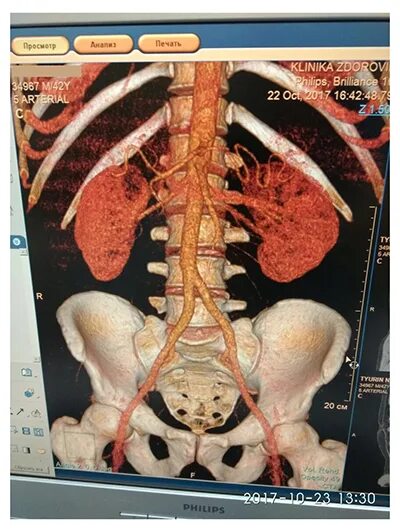

Кт почек с контрастированием как проводится